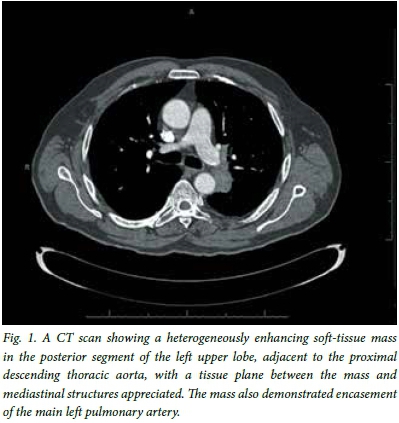

A 67-year-old man with a 40 pack-year smoking history presented with a 2-year history of hoarseness and weight loss. He also had a history of asbestos exposure. On examination under anaesthesia a lesion of the right false vocal fold was found and histology showed a moderately differentiated infiltrating keratinising squamous carcinoma. A subsequent computed tomography (CT) scan provisionally staged his supraglottic carcinoma as T2N0M0 and he underwent radical treatment with external beam radiation therapy, to which he responded well. He had been attending our clinic regularly and remained well, but on a visit 4 years later possible recurrence was considered - with hilar lymphadenopathy noted on his chest radiograph. On the CT scan of his chest there was a heterogenously enhancing soft-tissue mass (42 mm x 30 mm) in the posterior segment of the left upper lobe, adjacent to the proximal descending thoracic aorta, with a tissue plane between the mass and mediastinal structures appreciated. The mass demonstrated encasement of the left main pulmonary artery (Fig. 1). There was also a left diaphragmatic calcified plaque. The question posed was whether this mass could be ascribed to metastatic supraglottic carcinoma or if it was indeed a metachronous primary bronchus carcinoma, as the treatment of these two malignancies differs significantly. Considering traditional bronchoscopy with TBNA as the least invasive procedure to obtain a cytological diagnosis, the proximity of the aorta and pulmonary arteries and the mass being 14 mm from the bronchus would have made sampling by means of this procedure near impossible. With the assistance of EBUS the mass was localised, despite it not abutting the bronchus, and the position of the major vessels duly noted on Doppler ultrasound. Under real-time ultrasound guidance (Fig. 2) the tissue plane between the mass and bronchial lumen could be bridged by the longer EBUS needle to traverse safely between the major vessels, a window of <10 mm, and obtain a fine-needle aspirate of the mass. The result, which proved to be a keratinising squamous carcinoma (Fig. 3), was most likely of supraglottic origin. The patient was discharged the same day, with a follow-up appointment to see an oncologist.